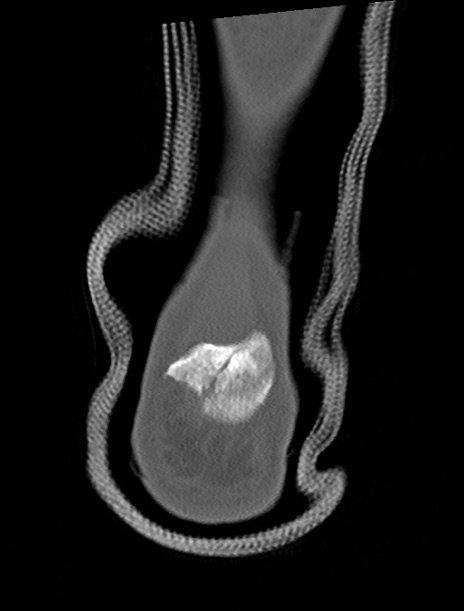

左足関節CT

横断像